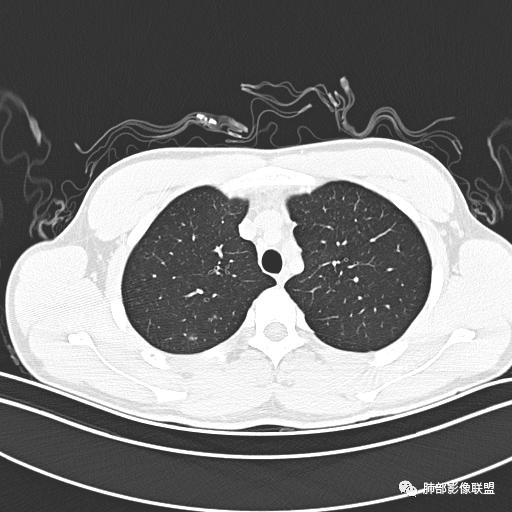

男,19岁

主  诉:发热、全身皮疹2天。

现病史:患者源于2天前受凉后出现发热,最高体温为38.5℃,且颜面部出现少量皮疹,无鼻塞、流涕、咳嗽、咳痰,未在意而未作特殊处理,次日全身皮疹逐渐增多至全身,伴轻度瘙痒,在当地卫生所给予抗病毒、抗感染治疗(具体用药不详)体温有所下降,但皮疹无明显消退,无腹痛、头痛,食欲无明显减退,为进一步诊治,遂于今日急来我院求治,患者目前精神尚可,体力正常,食欲正常,睡眠正常,体重无明显变化,大便正常,排尿正常。

小强:青年,发热,皮疹;双肺散在结节,周围磨玻璃,点晕征,疱疹病毒感染,鉴别荚膜组织胞浆菌,结核。 大雄:青年,急性起病,发热伴全身皮疹2天,抗病毒治疗体温有下降。双肺随机分布大小不等类圆结节,“点晕征”。考虑水痘-疱疹病毒(VZV)血播询问接触史,查体皮疹分布以及形态基本可诊断。 王开金江津中心医院呼吸科:青年男性,起病急,病程短,以发热,皮疹为首发症状,感染指标以单核细胞升高为主,胸部ct双肺多发结界,周围有晕,点晕表现,随机分布,同意於老师意见,水痘疱疹病毒血流感染累及肺。 王秀仙:双肺多发大小不等结节,周围有晕,边缘模糊,呈点晕征表现。青年,急性起病,发热伴全身皮疹2天,抗病毒治疗体温有下降。考虑疱疹病毒。鉴别荚膜组织胞浆菌。 傅昌瑜:19岁男性,发热、全身皮疹2天,单核细胞增高,双肺多发结节,结节边缘见边界不清磨玻璃影。点晕征+发热、全身皮疹+单核细胞增高——考虑水痘-带状疱疹病毒肺炎。 一切∮随缘:年轻男性,发热,皮疹两天,实验室,CRP,PCT增高,影像:双肺多发散在磨玻璃结节,边界欠清,大小不等,呈点晕征改变,以血管束周围分布为主,局部血管束略增粗,其它无明显改变,考虑:1:病毒性肺炎(水痘疱疹病毒?不知道皮肤有无改变)2:真菌(组织胞浆菌,血管侵袭性肺曲霉)3:GPA4:寄生虫(实验室没有看到嗜酸细胞增高) 赵山河:双肺散在结节,周围有晕,边缘模糊,呈点晕征表现。青年,急性起病,发热伴全身皮疹2天,抗病毒治疗体温有下降。考虑水痘—疱疹病毒感染。洪桥爱:青年男性,发热、皮疹2天,伴瘙痒,皮疹于面部首发,之后进展至全身,虽然没有对皮疹进行描述,但是从出疹时间及皮疹进展情况,伴瘙痒,应该就是个水痘患者;CT提示双肺随机分布结节影,部分结节伴有边界不清晕征,考虑水痘血播肺。 刘强:年轻男性,急性起病,皮疹,发热,抗感染治疗体温下降,说明有效。影像表现为散在点晕征,感染类疾病谱(疱疹病毒,真菌,结核),结合年龄,皮肤皮疹,考虑水痘-疱疹病毒性肺炎。 小兜:男性,19岁,发热皮疹两天,颜面部至全身,CRP,降钙素及单核增高。CT示双肺散在小结节,周围伴磨玻璃影,点晕征,考虑为水痘-带状疱疹病毒(varicella-zoster virus,VZV)肺炎 必有路:青年,皮疹+发热+“点晕征”→水痘-疱疹病毒(VZV) 许慧良:青年男性患者,发热、皮疹2天,体温最高38.5℃,第3天皮疹扩展至全身,伴瘙痒,胸部CT:双肺多发随机分布的小结节,结节周边见边界模糊的晕征,考虑水痘病毒感染流心明智:男,19,急性起病,发热伴全身皮疹2天。出疹顺序头→全身,抗病毒有效。胸部CT:两肺多发大小不等类圆形实性小结节影,随机分布,结节周围环绕GGO,边界模糊,呈点晕征。出疹特点是关键,未提示。考虑:血播病毒性肺炎,水痘-疱疹病毒?麻疹?鉴别荚膜组织胞浆菌、TB、血管炎、寄生虫等。 浪迹天涯:病灶多为5-10mm大小结节,结节周围可见磨玻璃样的晕环,常多发,可分布于肺内任何区域,考虑水痘—带状疱疹病肺炎如果短时间内有新的一个区域浸润,更加能说明,